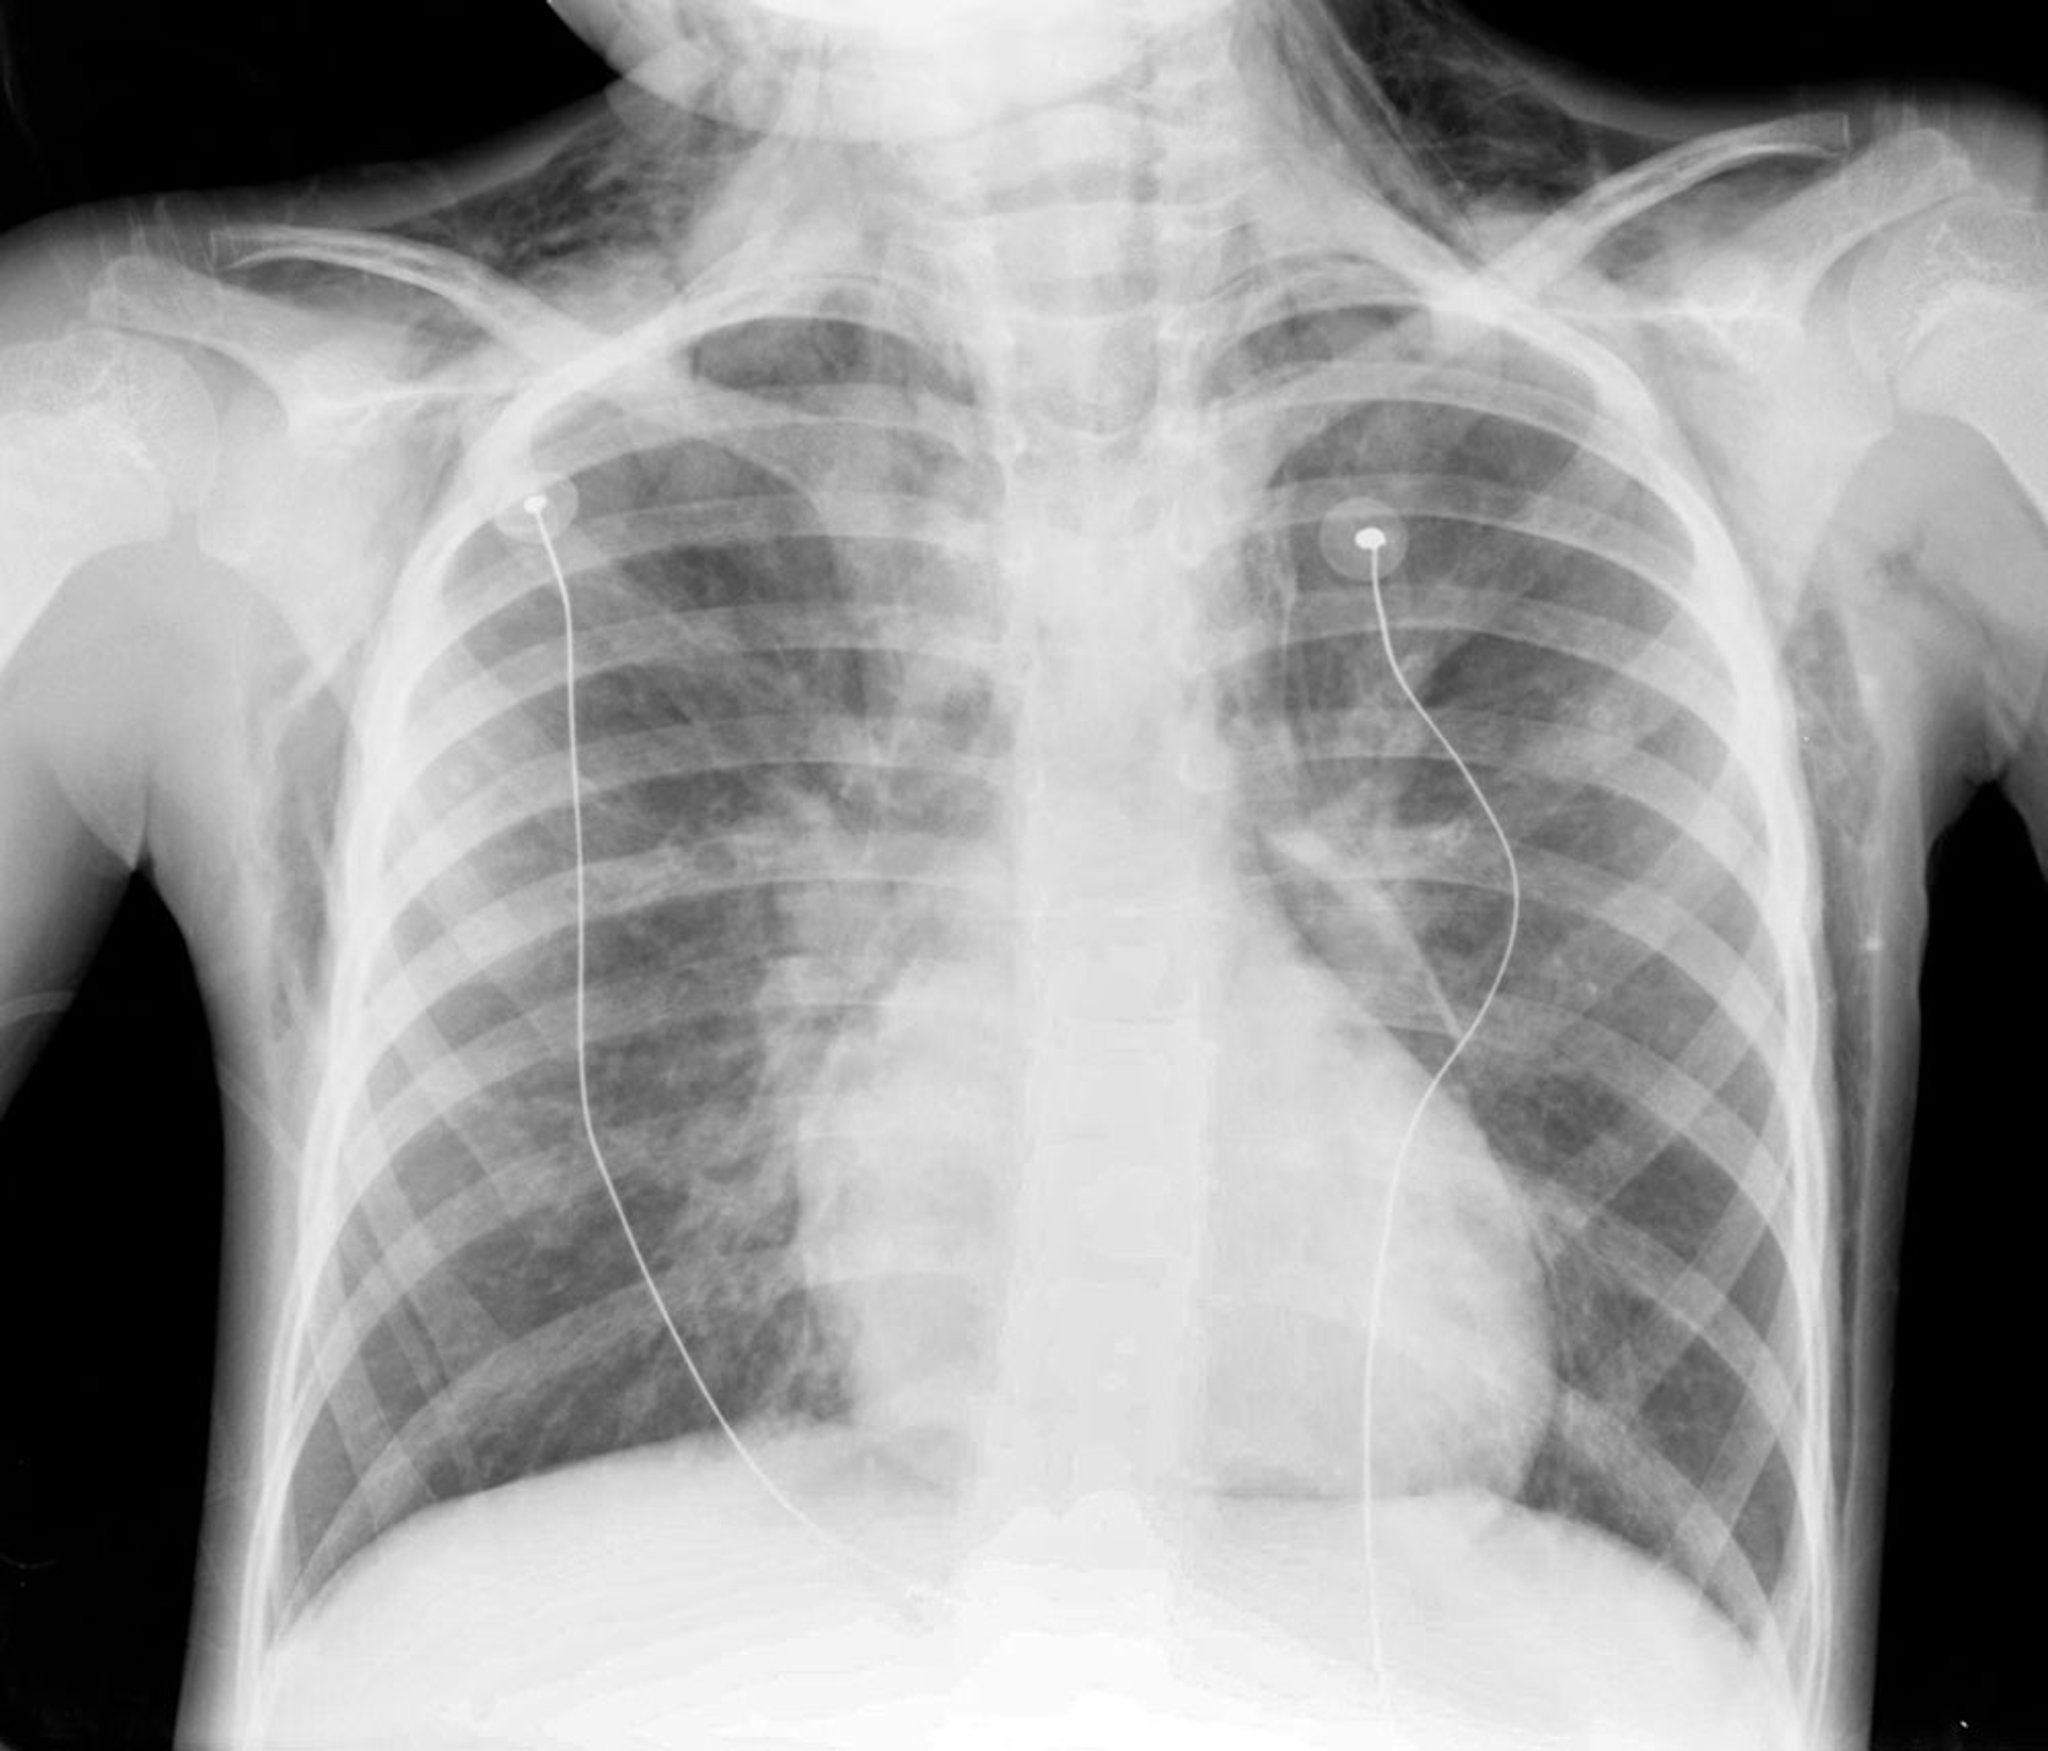

El neumomediastino es la presencia de aire en los intersticios mediastínicos.

El diagnóstico se confirma mediante radiografía de tórax, que muestra aire en el mediastino.